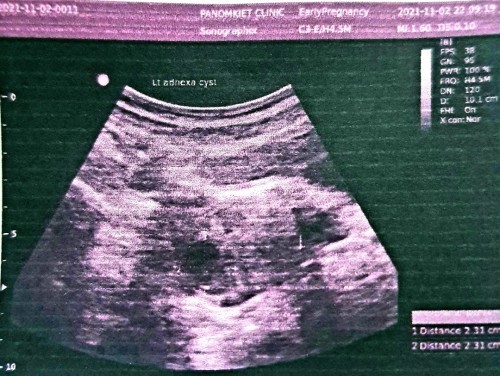

ของแม่บ้านนี้7วีคค่ะไปตรวจเมื่อวานก็ยังไม่เจอน้องเลยค่ะคุณหมอนัดตรวจซ้ำอีก2อาทิตย์ตอนนี้ลุ้นมากๆ

บ้านนี้ตรวจเจอท้องตอน 5 วีค ไปซาวเจอแต่ถุงตั้งครรภ์ พอ 6 วีค ไปหาคุณหมอซาวด์เจอน้องและเสียงหัวใจเต้นค่ะ

ตรวจครั้งแรกตอน5วีคเจอแต่ถุงการตั้งครรภ์ หมอนัดอีกรอบตอน9วีคเจอน้องและเสียงหัวใจเต้นเร็วมากค่ะ

7w3dเจอแต่ถุงตั้งครรภ์ยังไม่เจอตัวน้องคะหมอบอกว่าน้องยังเล็กมากประมาณ5mmนัดซาวอีกที28กันยา